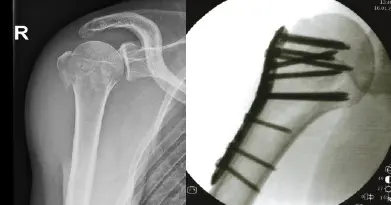

Abbildung: Versorgung einer 3-Part-Fraktur des Oberarmkopfes mittels winkelstabiler Platte.